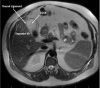

Biliary colic is a pain in the right upper quadrant or epigastrium thought to be caused by functional gallbladder spasm from a temporary obstructing stone in the gallbladder neck, cystic duct or common bile duct. A 56-year-old man presented with frequent episodes of typical biliary colic. At initial laparoscopy, the gallbladder was absent from its anatomic location. Further inspection revealed a left-sided gallbladder (LSGB), suspended from liver segment 3. Preoperative ultrasound, the most common imaging modality for symptomatic gallstones, has a low positive predictive value for detecting LSGB (2.7%). Laparoscopic cholecystectomy (LC) was delayed to attain additional imaging. A magnetic resonance cholangiopancreatography demonstrated the gallbladder left of the falciform ligament with the cystic duct entering the common hepatic duct from the left. The patient underwent an elective LC 8 weeks later. The critical view of safety is paramount to safe surgical dissection and could be safely achieved for LSGB.